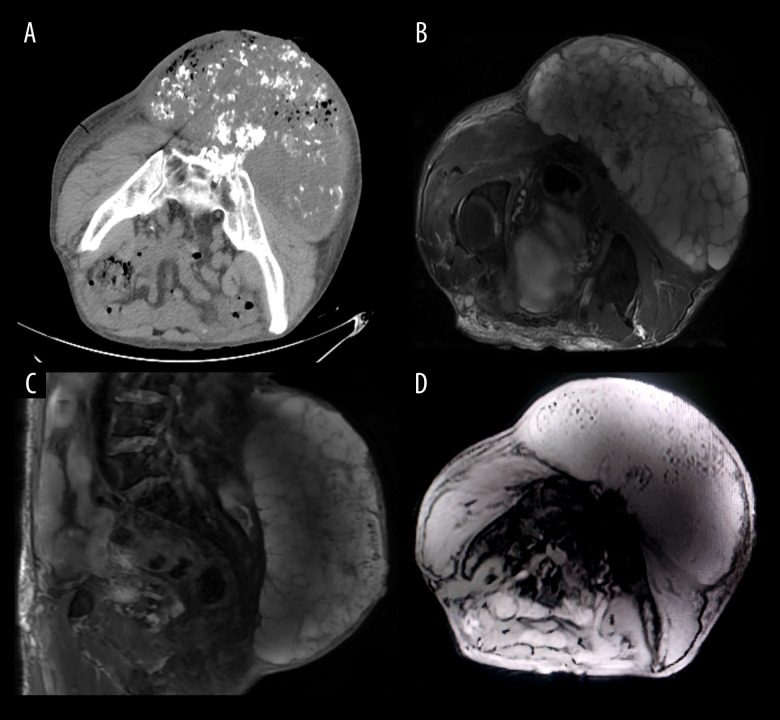

BACKGROUND Extraskeletal chondrosarcoma is a rare soft tissue sarcoma with no characteristic imaging and clinical manifestations. Therefore, early preoperative diagnosis is difficult and ultimately depends on postoperative pathology and genetic diagnosis. CASE REPORT A 67-year-old man presented with a huge buttock tumor. The maximum transverse section length of the tumor was 40 cm. Due to the large size and long duration of the tumor, the tumor ruptured and invaded part of the sacrum. The preoperative diagnosis was not clear, the tumor was completely removed by surgery, and the wound was repaired. Adjuvant radiotherapy was given after surgery, and the prognosis was good. CONCLUSIONS This case report demonstrates the importance of radical surgical resection and postoperative adjuvant chemotherapy for the prognosis of extraosseous chondrosarcoma. It also suggests that sometimes the early diagnosis of this type of tumor is difficult, depending on postoperative pathology and genetic diagnosis.